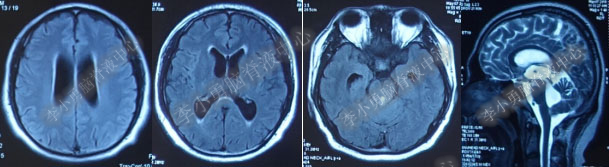

2016年5月9日因“间断性眩晕半月,恶心呕吐一周”以“梗阻性”脑积水,第1次住入北京某企业三级医院神经外科内镜组。2016年5月10日(入院后第2天)行头部MRI(图-1)检查示脑室系统扩张。

图-1:2016年5月10日头部MR